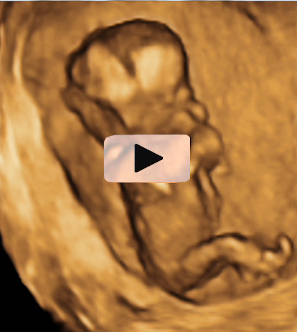

La ausencia de hueso nasal y tener un pliegue nucal aumentado son marcadores que se detectan en la ecografía de la semana 12 y que pueden significar que el feto padece alguna alteración cromosómica, como es el síndrome de Down.

En A se aprecia el hueso nasal (flecha) en una gestación normal de 12 semanas. En B, un embrión de 12 semanas con síndrome de Down, en el que el hueso nasal está ausente y además tiene una translucencia nucal aumentada.

Ecografía Embarazo 2D y 3D Semana 12 - PRUEBAS DIAGNÓSTICAS

Imagen del hueso nasal ausente (A) y pliegue nucal aumentado (B)